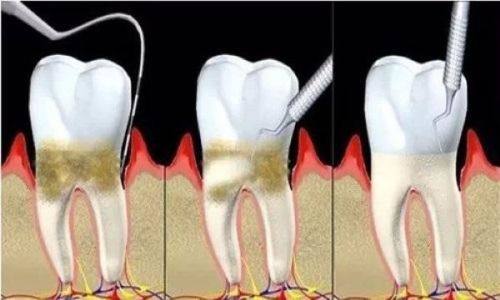

1. 中医和西医结合治疗:采用中医和西医结合的方式治疗各种口腔粘膜病和牙周病,将中医的整体调理与西医的精细治疗相结合,成效显著。

3. 全领域诊疗:开展口腔内科、口腔修复、牙槽外科、口腔正畸等所有诊疗项目,能满足患者多样化的口腔需求。

1. 根管治疗术:800 - 1500元

2. 牙周治疗:500 - 1200元